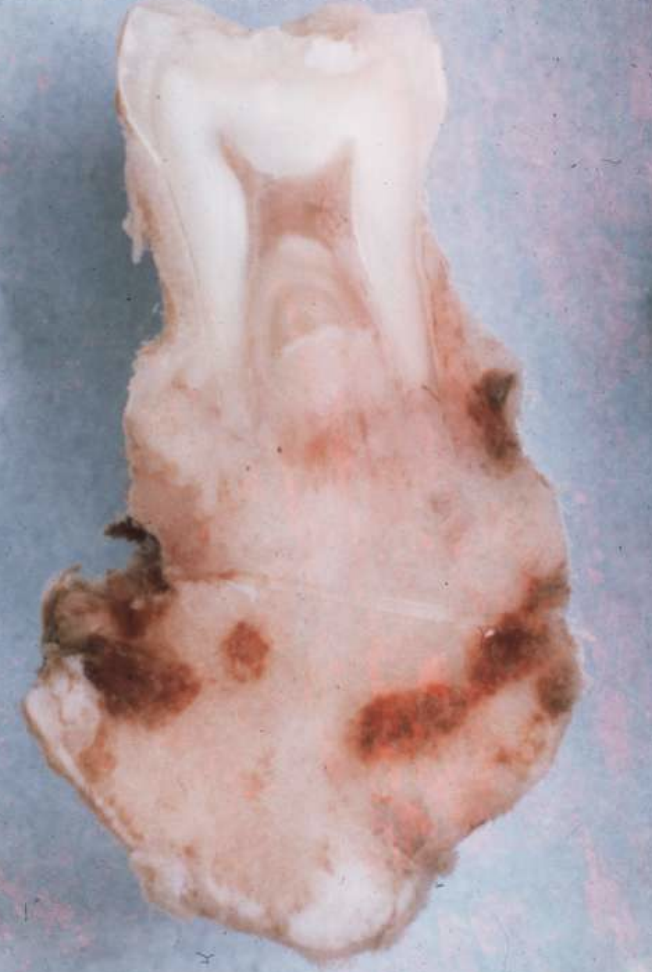

what are histopathologic features of complex odontomas?

• mature tubular dentin with structures that contained enamel before decalcification

• 20% show ghost cells

• thin layer of cementum around mass